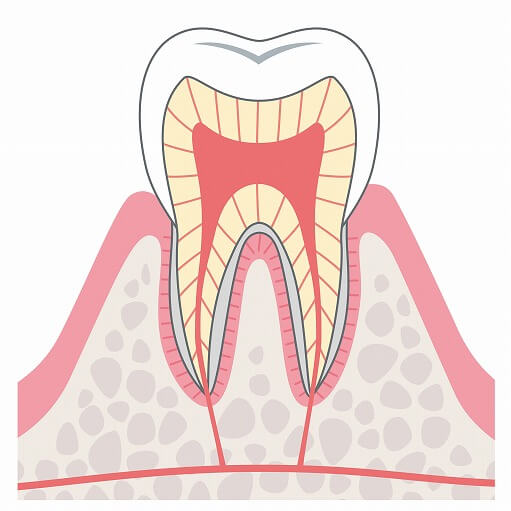

むし歯の進行状態

C0

痛みがなく自覚症状も見られずむし歯の治療としてフッ素塗布やブラッシング、予防治療をで問題ありません。

痛みがなく自覚症状も見られずむし歯の治療としてフッ素塗布やブラッシング、予防治療をで問題ありません。

このときに歯科医院に通うことで歯を抜かない・削らないで長くご自身の歯を大切に使うことができます。

C1

C1は初期状態のむし歯で、歯の表面のエナメル質に少し穴が空いた状態です。むし歯部分が黒、茶色く見えることもありますがこの状態では痛みや症状もないため、むし歯とは気づかないことが多いです。

C1は初期状態のむし歯で、歯の表面のエナメル質に少し穴が空いた状態です。むし歯部分が黒、茶色く見えることもありますがこの状態では痛みや症状もないため、むし歯とは気づかないことが多いです。

C2

C2はC1より更に進行した状態のむし歯で、エナメル質より下の層の象牙質にまでむし歯が広がってしまった状態です。冷たいものや熱いものが染みることもありますが、このような症状を感じない場合もあります。C2の状態なら3回ほどで治療を終えられることがほとんどです。

C2はC1より更に進行した状態のむし歯で、エナメル質より下の層の象牙質にまでむし歯が広がってしまった状態です。冷たいものや熱いものが染みることもありますが、このような症状を感じない場合もあります。C2の状態なら3回ほどで治療を終えられることがほとんどです。

C3

C3は象牙質を突き抜け、歯の神経(歯髄)にまでむし歯が進行してしまった状態です。冷たいものや熱いものが染みるだけでなく、夜眠れないほどの強い痛みが出る場合もあります。C3の状態まで達してしまうと歯の神経への治療が必要となるため、治療回数は多くなります。

C3は象牙質を突き抜け、歯の神経(歯髄)にまでむし歯が進行してしまった状態です。冷たいものや熱いものが染みるだけでなく、夜眠れないほどの強い痛みが出る場合もあります。C3の状態まで達してしまうと歯の神経への治療が必要となるため、治療回数は多くなります。

C4

C4はむし歯が進行してしまったことにより歯の頭が崩れ落ちてしまい、歯の根だけが残っている状態です。歯の神経が死んでしまっているため痛みが無い場合もありますが、歯の根の奥にまでむし歯菌が到達すると激痛が起こることもあり、場合によってや顔の腫れや高熱が出ることもあります。進行度合いによっては歯を抜かないといけないことがあります。

C4はむし歯が進行してしまったことにより歯の頭が崩れ落ちてしまい、歯の根だけが残っている状態です。歯の神経が死んでしまっているため痛みが無い場合もありますが、歯の根の奥にまでむし歯菌が到達すると激痛が起こることもあり、場合によってや顔の腫れや高熱が出ることもあります。進行度合いによっては歯を抜かないといけないことがあります。